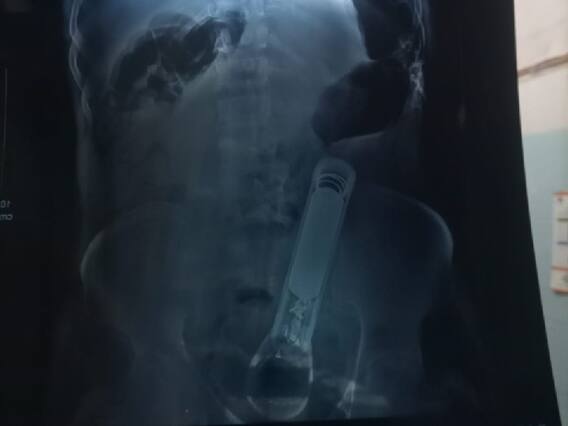

मामला मांझागढ़ थाना क्षेत्र का है. पुलिस ने इस मामले में प्राथमिकी दर्ज कर एक आरोपित को गिरफ्तार कर लिया है, वहीं अन्‍य आरोपितों की गिरफ्तारी के लिए छापेमारी कर रही है. दूसरी ओर पीड़ित को परिवार वालों ने इलाज के लिए स्‍थानीय सरकारी अस्‍पताल में भर्ती कराया, जहां से डॉक्‍टरों ने गोरखपुर रेफर कर दिया. इसके बाद परिजन उसे एक निजी अस्‍पताल में ले गए, जहां पेट में फंसे टॉर्च को ऑपरेशन कर बाहर निकाला गया.

बताया जा रहा है कि 26 जून की रात में गांव में बर्थडे पार्टी था. पीड़ित युवक को चार लोग बुलाने के लिए घर पर आए थे, वहां जाने पर वे लोग नाचने के लिए कहने लगे. युवक के इंकार करने पर मारपीट की गयी. इसी दौरान चारों युवकों ने मिलकर लोहे की टॉर्च को प्राइवेट पार्ट से डाल दिया. पीड़ित ने घर आकर पूरी घटना जब अपनी पत्नी और परिजनों को बताई तो उसे तत्‍काल इलाज के लिए अस्पताल ले जाया गया, जहां डॉक्टरों ने गोरखपुर रेफर कर दिया. वहीं, इस मामले में पुलिस ने पीड़ित की शिकायत पर प्राथमिकी दर्ज कर ली है. एक आरोपी उमेश्वर साह को गिरफ्तार किया गया है. जबकि सोनू साह समेत अन्य आरोपी फरार है. पुलिस के मुताबिक जल्द ही सभी आरोपितों की गिरफ्तारी कर ली जायेगी. पुलिस फरार आरोपितों के ठिकानों पर लगातार छापेमारी कर रही है.